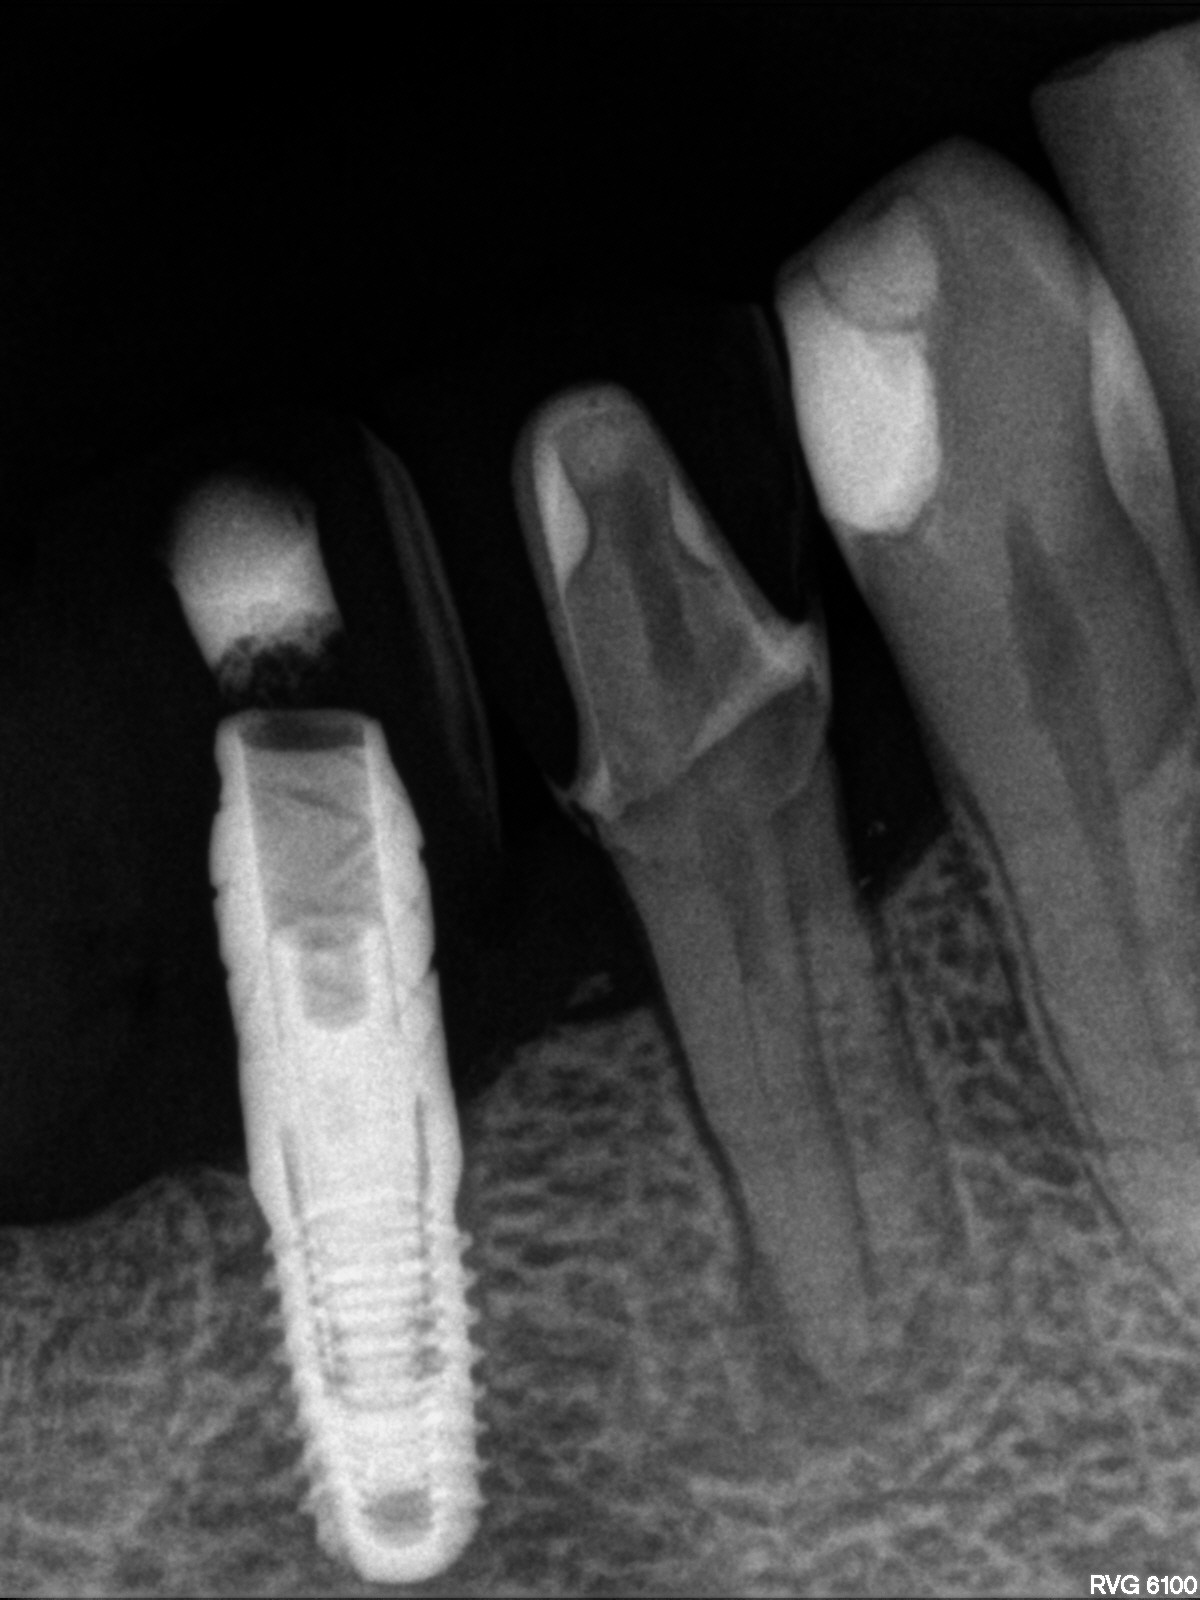

Prämolar mit Hürden